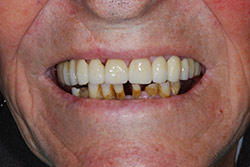

Riabilitazione implanto - protesica superiore ed inferiore in un paziente di 84 anni

Con protesi fissa superiore e protesi fissa inferiore

I denti irrecuperabili dell'arcata superiore ed inferiore del paziente di anni 65 sono stati sostituiti da 10 impianti, cioè protesi radicolari endo-ossee che sostengono le protesi fisse superiore ed inferiore.